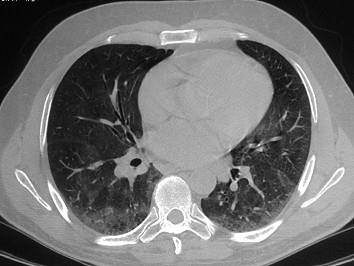

问题 患者因反复咳浓臭痰2年入院,胸部CT如图所示,最有可能的诊断是 ( )

选项 A、肺癌 B、以上均不正确 C、肺结核 D、支气管扩张 E、脓胸

答案 D